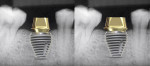

Tissue-level and non-platform-switched implants typically are not placed below the bone level (subcrestal) (Figure 3).22 Placement of such implants below the bone level is not recommended, as the bone will remodel leading to crestal bone loss in a saucerization pattern.11 This occurs in tissue-level implants because the smooth collar of the implant is not roughened for osseointegration. In non-platform-switched implants, subsequent placement of the abutment below bone level leads to remodeling circumferentially to accommodate biological width development (Figure 4).23